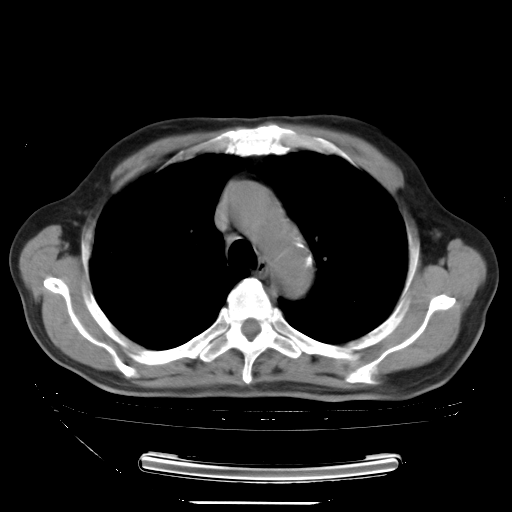

今天复查肺部CT,发现双肺广泛磨玻璃样改变。所以我把3月19日和5月9日相隔50天的肺部CT上传。请大家会诊。

5月9日肺部CT(在4月27日齐鲁医院肺部CT描述部分肺组织磨玻璃样改变,12天后肺组织广泛磨玻璃样改变)

2009年5月9日肺部CT

大致读了系列胸部CT:纵隔窗无明显异常,肺窗:从4、27至今:主要是双肺中下野外带可见毛玻璃样改变,目前处于急性肺泡炎阶段,至于原因考虑1、结替组织或胶原血管性疾病所致?2、恶性疾病如恶组在肺部所致的表现或细支气管肺泡癌?3、药物或其它原因如肺蛋白沉着症所致肺泡炎目前不太可能?总之,明天就去请我院的呼吸科、感染科、血液科和临免专家会诊哈。